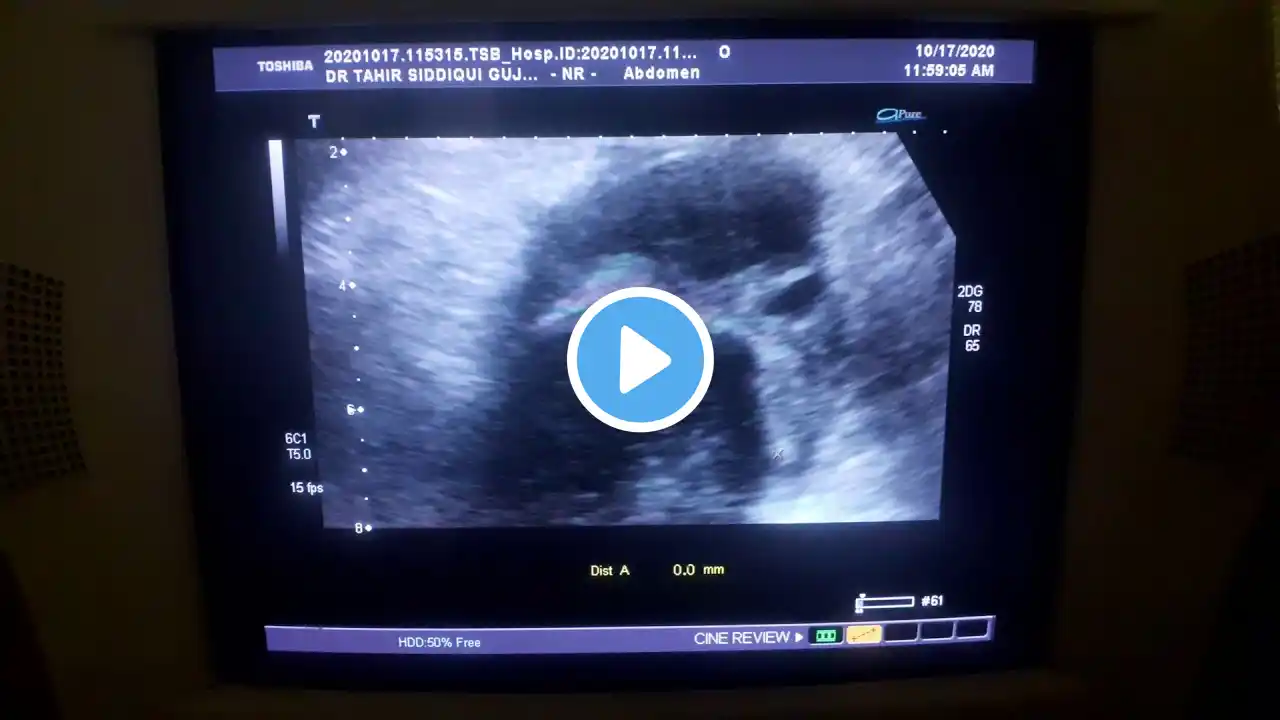

Thick-walled Gallbladder, Hepatic Mass with Hepatic parenchymal disease and ascites.

Thick-walled Gallbladder, Hepatic Mass with Hepatic parenchymal disease and ascites. Hepatic tumors are a diverse group of masses that include malignant and benign subtypes. Their presentation may vary from localizing signs/symptoms, such as jaundice and right upper quadrant pain, to vague signs/symptoms, such as fatigue, weight loss, and anorexia. Many hepatic tumors are discovered incidentally on medical imaging studies. Moreover, the liver is a common site for metastasis, and metastases to the liver are significantly more common than primary liver tumors. The incidence of primary liver cancer is steadily increasing worldwide. Unlike most other causes of liver disease, it is treatable and the prognosis is excellent provided that it is diagnosed before irreversible damage has occurred. The most common causes of cirrhosis are hepatitis and other viruses. Alcohol abuse. Nonalcoholic fatty liver disease (this happens from metabolic syndrome and is caused by conditions such as obesity, high cholesterol and triglycerides, and high blood pressure), Most benign liver tumors do not cause symptoms and are found incidentally on abdominal imaging studies such as an ultrasound, CT scan, or MRI. It is important that benign tumors are not misdiagnosed. Your doctor may choose to follow the tumor with imaging studies to ensure that they have been diagnosed correctly. Globally, liver cancer is the third leading cause of cancer death after cancers of the lung and the stomach. The highest incidence of hepatocellular carcinoma (HCC) is in China, representing about 50% of HCC cases worldwide, with most of the cases associated with hepatitis B virus (HBV) infection. Cholangiocarcinoma also has a disproportionate geographical distribution, with Thailand having the highest global rates due to the presence of liver flukes. Accurate characterization of liver masses by cross-sectional imaging is liver disease with cirrhosis, portal hypertension, and hypersplenism. Focal fat is also hyperechoic to the normal liver parenchyma on ultrasound. Coarsened hepatic echotexture is a sonographic descriptor used when the uniform smooth hepatic echotexture of the liver is lost. This can occur due to a number of reasons which include: conditions that cause hepatic fibrosis. Liver lesions are groups of abnormal cells in your liver. Your doctor may call them a mass or a tumor. Noncancerous, or benign, liver lesions are common. They don't spread to other areas of your body and don't usually cause any health issues. But some liver lesions form as a result of cancer. Either a single tumor larger than 2 cm (4/5 inch) that has grown into blood vessels, OR more than one tumor but none larger than 5 cm (about 2 inches) across. It has not spread to nearby lymph nodes or to distant sites. More than one tumor, with at least one tumor larger than 5 cm across. Fetor hepaticas occur when your breath has a strong, musty smell. It's a sign that your liver is having trouble doing its job of filtering out toxic substances, usually due to severe liver disease. As a result, sulfur substances end up in your bloodstream and can make their way to your lungs.